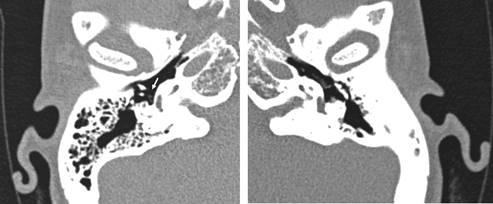

Femenino de 22 años con hipoacusia conductiva en oído izquierdo de más de 10 años de evolución. A la exploración física y la otoscopia: pabellones auriculares y membranas timpánicas normales; prueba de Rinne positiva en OD derecho y negativa en OI; prueba de Weber lateralizada a OI. la audiometría tonal entre 20-40 dB, mayor en frecuencias graves y con presencia de la muesca de Carhart a los 2000 Hz en la vía ósea ipsilateral; la impedanciometría con reflejos ipsi y contralaterales con estímulo de 100 dB mostró curvas timpanométricas normales y reflejos ipsilaterales y contralaterales ausentes en OI e ipsilaterales positivos y contralaterales ausentes en OD derecho. La tomografía computarizada mostró agenesia del proceso largo del yunque y del estribo izquierdo, sin cruras, presente la platina (Figuras 1 y 2).

Figura 1: Tomografía computarizada de oídos con reconstrucción coronal, en el lado derecho se aprecia al proceso largo del yunque, la articulación incudoestapedial y al estribo en la ventana oval (flecha); en el lado izquierdo existe agenesia de estas estructuras.